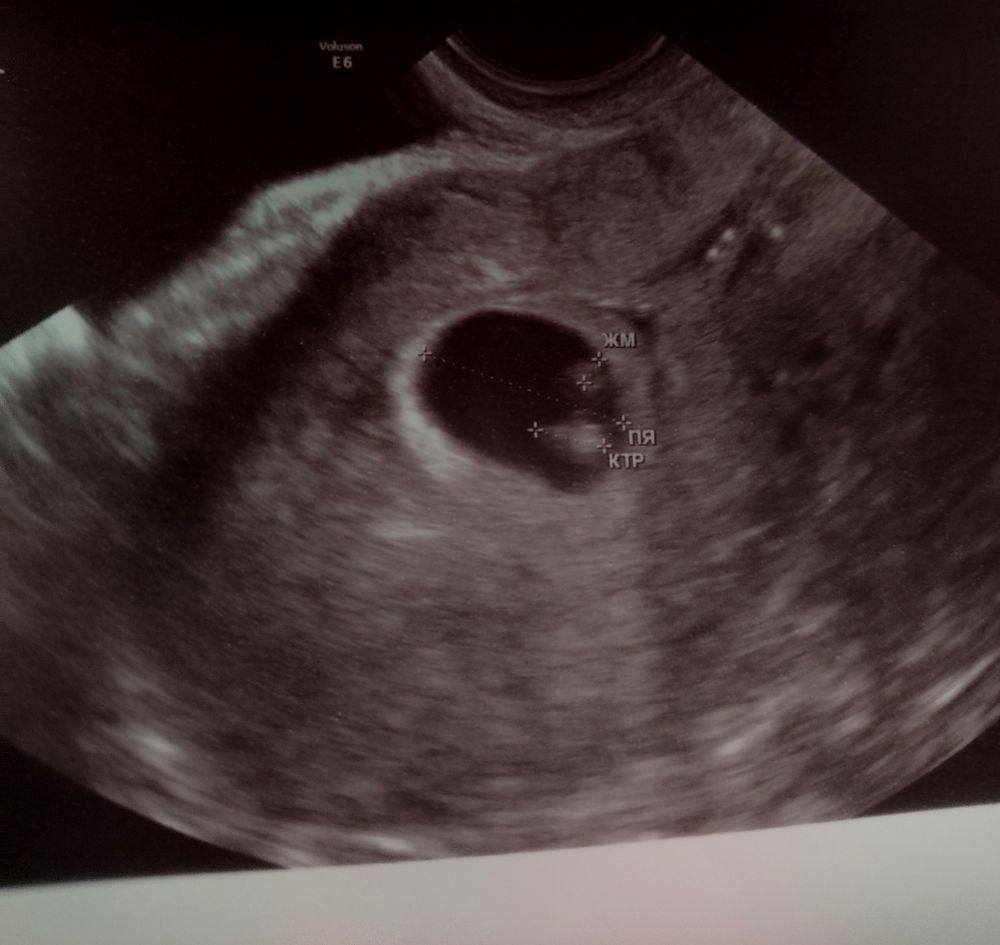

УЗИ 7 недель ❤️

Сходила на второе УЗИ, первое делала на сроке 6 недель ровно, тогда эмбриончика не увидели.

Так вот, вчера все увидели и дали послушать сердечко 129 уд/мин, я аж заплакала. Ещё и отслойки, которую обнаружили на прошлом УЗИ, больше нет 🎉